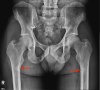

Phosphaturic mesenchymal tumors (PMT) are a rare neoplasm oftentimes associated with tumor-induced osteomalacia (TIO). The non-specific presentation and symptoms of these pathologies make them difficult to diagnose. We report a case of a 52-year-old patient with an intermetatarsal phosphaturic mesenchymal tumor who presented to the orthopedic sports medicine clinic with metabolic deficiencies and bilateral subtrochanteric cortical stress fractures indicative of osteomalacia. The tumor was entirely resected within nine months of symptom onset and has shown no recurrence at the one-year follow-up. This case report characterizes an unusual cause of stress fractures presenting to orthopedic sports medicine clinics and the variability in the presentation of phosphaturic mesenchymal tumors.